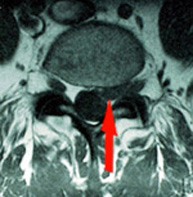

- RMN. Esta prueba es concluyente en la mayoría de los casos y además de esclarecer el

tipo, situación de la hernia descarta otras lesiones tipo quiste y tumores que también son causa de ciática de forma excepcional. - TC. Cuando existan dudas es una prueba a realizar ya que aporta mejor información de las alteraciones óseas.